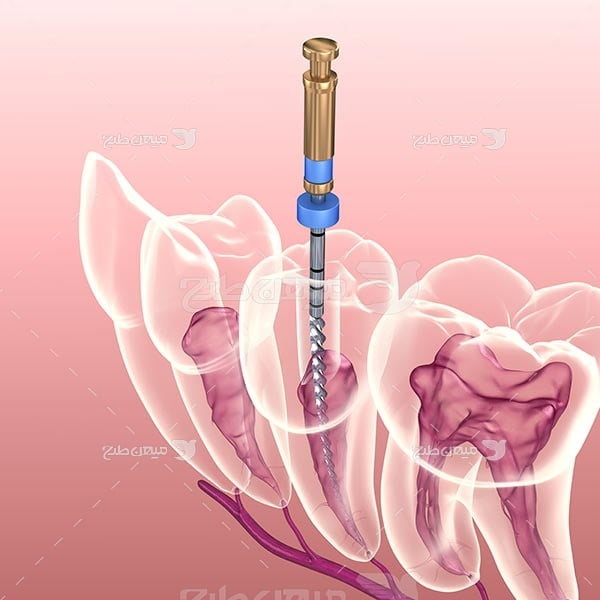

- عصب کشی موضعی با کمترین هزینه

عصب کشی

هانیه :من عصب کشی دندان انجام دادم کاملا بدون درد بود و بعدش اصلا اذیت نشدم خیلی راضیم ممنون

سولماز: دست خانم دکتر خیلی سبکه بی حسی هاشون واقعا درد نداره